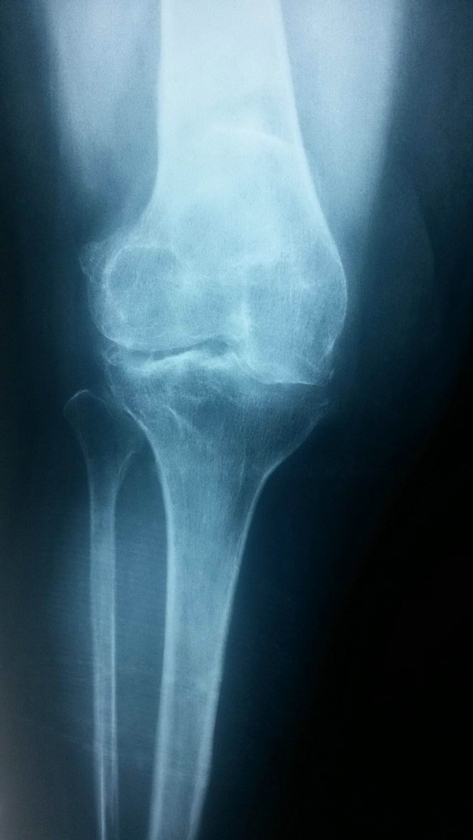

1.膝关节发病机理

膝关节支撑着人体重量的80%,当负重额外增加(如挑担、搬运、提重物等),或偶尔病毒侵入膝关节周围的肌束、滑膜等组织,引起相应周围的软组织,腘部血管、韧带等产生无菌性炎症疼痛或局部水肿。随着年龄的增长,内分泌功能变化,膝关节腔受到支撑力影响而发生变化。原先的膝关节正常支撑点,逐渐形成了新的错位支撑力点。此也多半由于胫腓韧带积累性的劳损,最先发生变化,引起支撑点外向侧飘移,促使膝关节腔内结构组织的痉挛,形成内侧半月板磨损或率先发生半月板破损,使膝关节骨性结构变得越来越狭窄。腘部的腘肌与静脉相应受到影响,最终发生了功能障碍和疼痛。伴随着就会出现股骨头、膝关节、踝关节形成病态角度。因而也会导致髋关节、踝关节的力点飘移,也产生相应的疼痛。